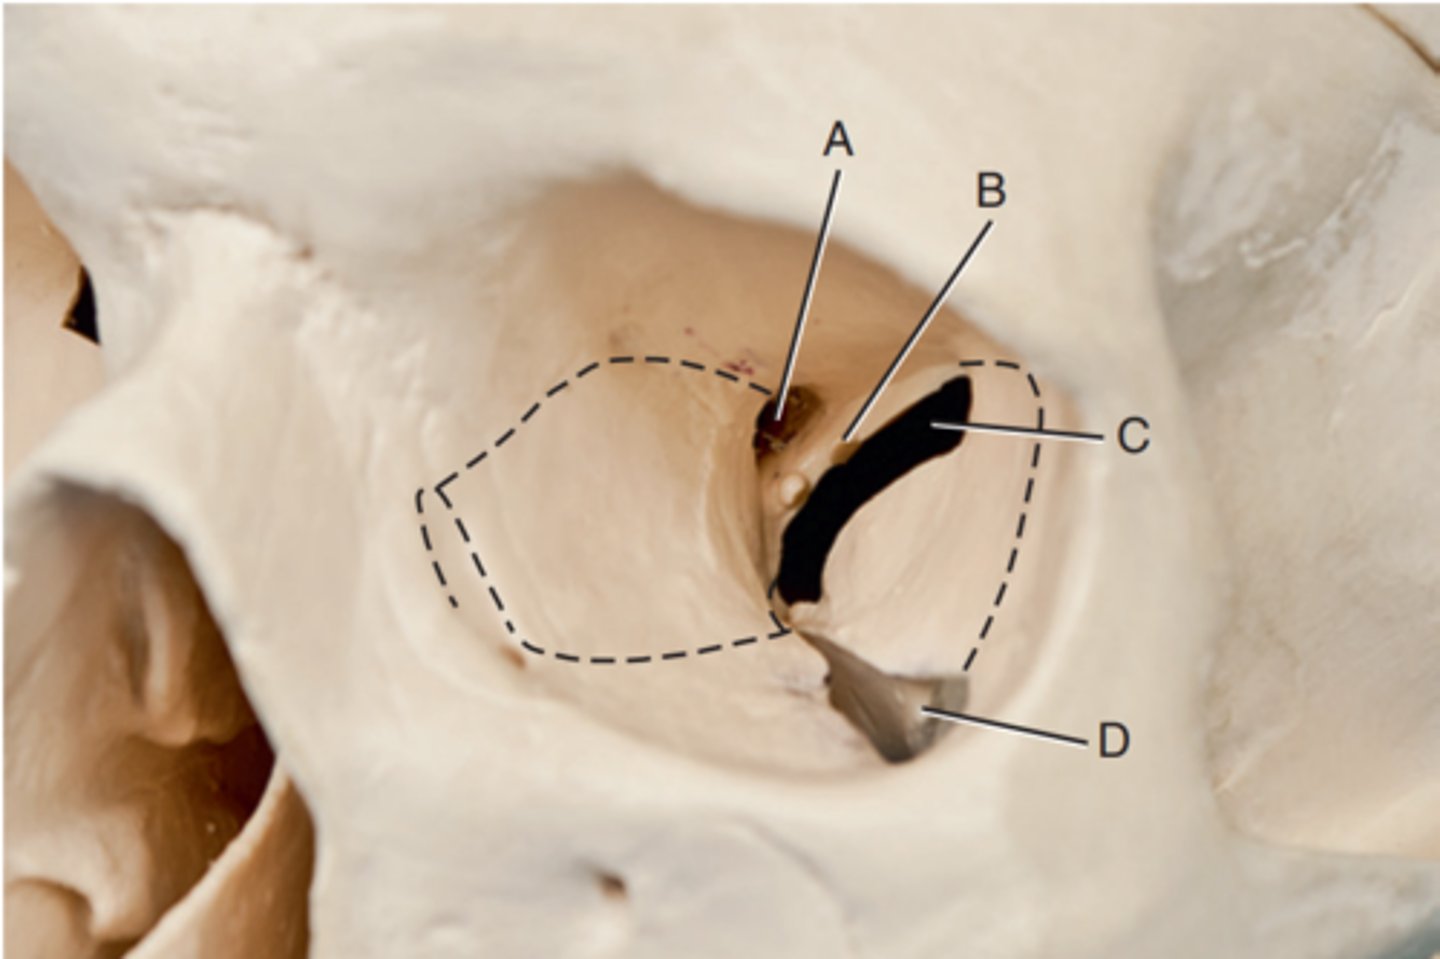

Optic foramen

Label A

Sphenoid strut

Label B

Superior orbital fissure

Label C

Inferior orbital fissure

Label D

Orbital plate of frontal bone

Label A

Sphenoid bone

Label B

Optic foramen and canal

Label C

Superior orbital fissure

Label D

Infraorbital margin (IOM)

Label E

Sphenoid strut

Label F

Lateral orbital margin

Label G

Supraorbital margin

Label H